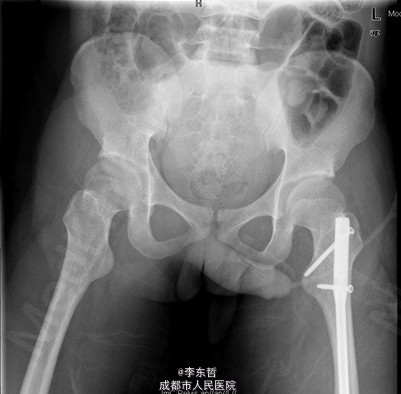

患者男,19岁,因“车祸伤致左下肢活动障碍5小时”入院。5小时前,患者骑电瓶车不慎与另一电动摩托车相撞倒地,当即感左大腿疼痛,畸形,活动受限,右小腿皮肤挫伤、出血,无头晕头痛,无大小便失禁。就诊于当地医院,检查提示:左股骨中段横行骨折。急诊行左大腿夹板外固定,右小腿清创缝合术,术后未进一步治疗,患者为进一步诊治来我院,急诊以左股骨中段骨折收入我科。 自患病以来,患者一般情况尚可,精神睡眠可,小便正常,大便未解。

查体:左大腿夹板固定,肿胀明显,短缩、畸形,右小腿内前方可见一长约5cm创口,已缝合,内植引流条一根,无明显肿胀。左大腿中段环周压痛,可扪及骨折断端,右小腿无明显压痛,双下肢感觉正常。左膝及髋关节明显活动受限,左足背及右下肢活动正常。 辅查:外院X片示:左侧股骨中上段可见骨质断裂征象,断端分离、错位、重叠,周围软组织肿胀;双侧胫腓骨、左膝关节各骨及左踝关节未见确切骨质断裂征象。

初步诊断:1、左股骨中段横行骨折,2、右小腿皮肤软组织裂伤清创缝合术后。 诊疗计划:1、向患者及家属交待病情及注意事项。2、向上级医生汇报患者病情。3、完善术前相关检查。4、给予皮肤牵引、抬高患肢等对症处理。5、拟进一步手术治疗。6、密切观察病情变化,根据病情及时处理